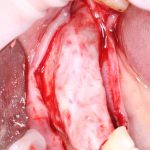

Вот клиническая картина через 4 месяца после ранее проведенной имплантации с остеопластикой:

Как видишь, коллеги из недалекой дружественной страны не осилили снятие швов. Мне это не нравится, хотя и объясняет, почему люди готовы ехать за тыщи километров ради 20-минутной операции удаления зуба мудрости.

Ну хорошо. Швы сняли. Делаем разрез. Обрати внимание, что после всех проведенных операций у нас остается очень небольшой по ширине слой жевательной слизистой оболочки: